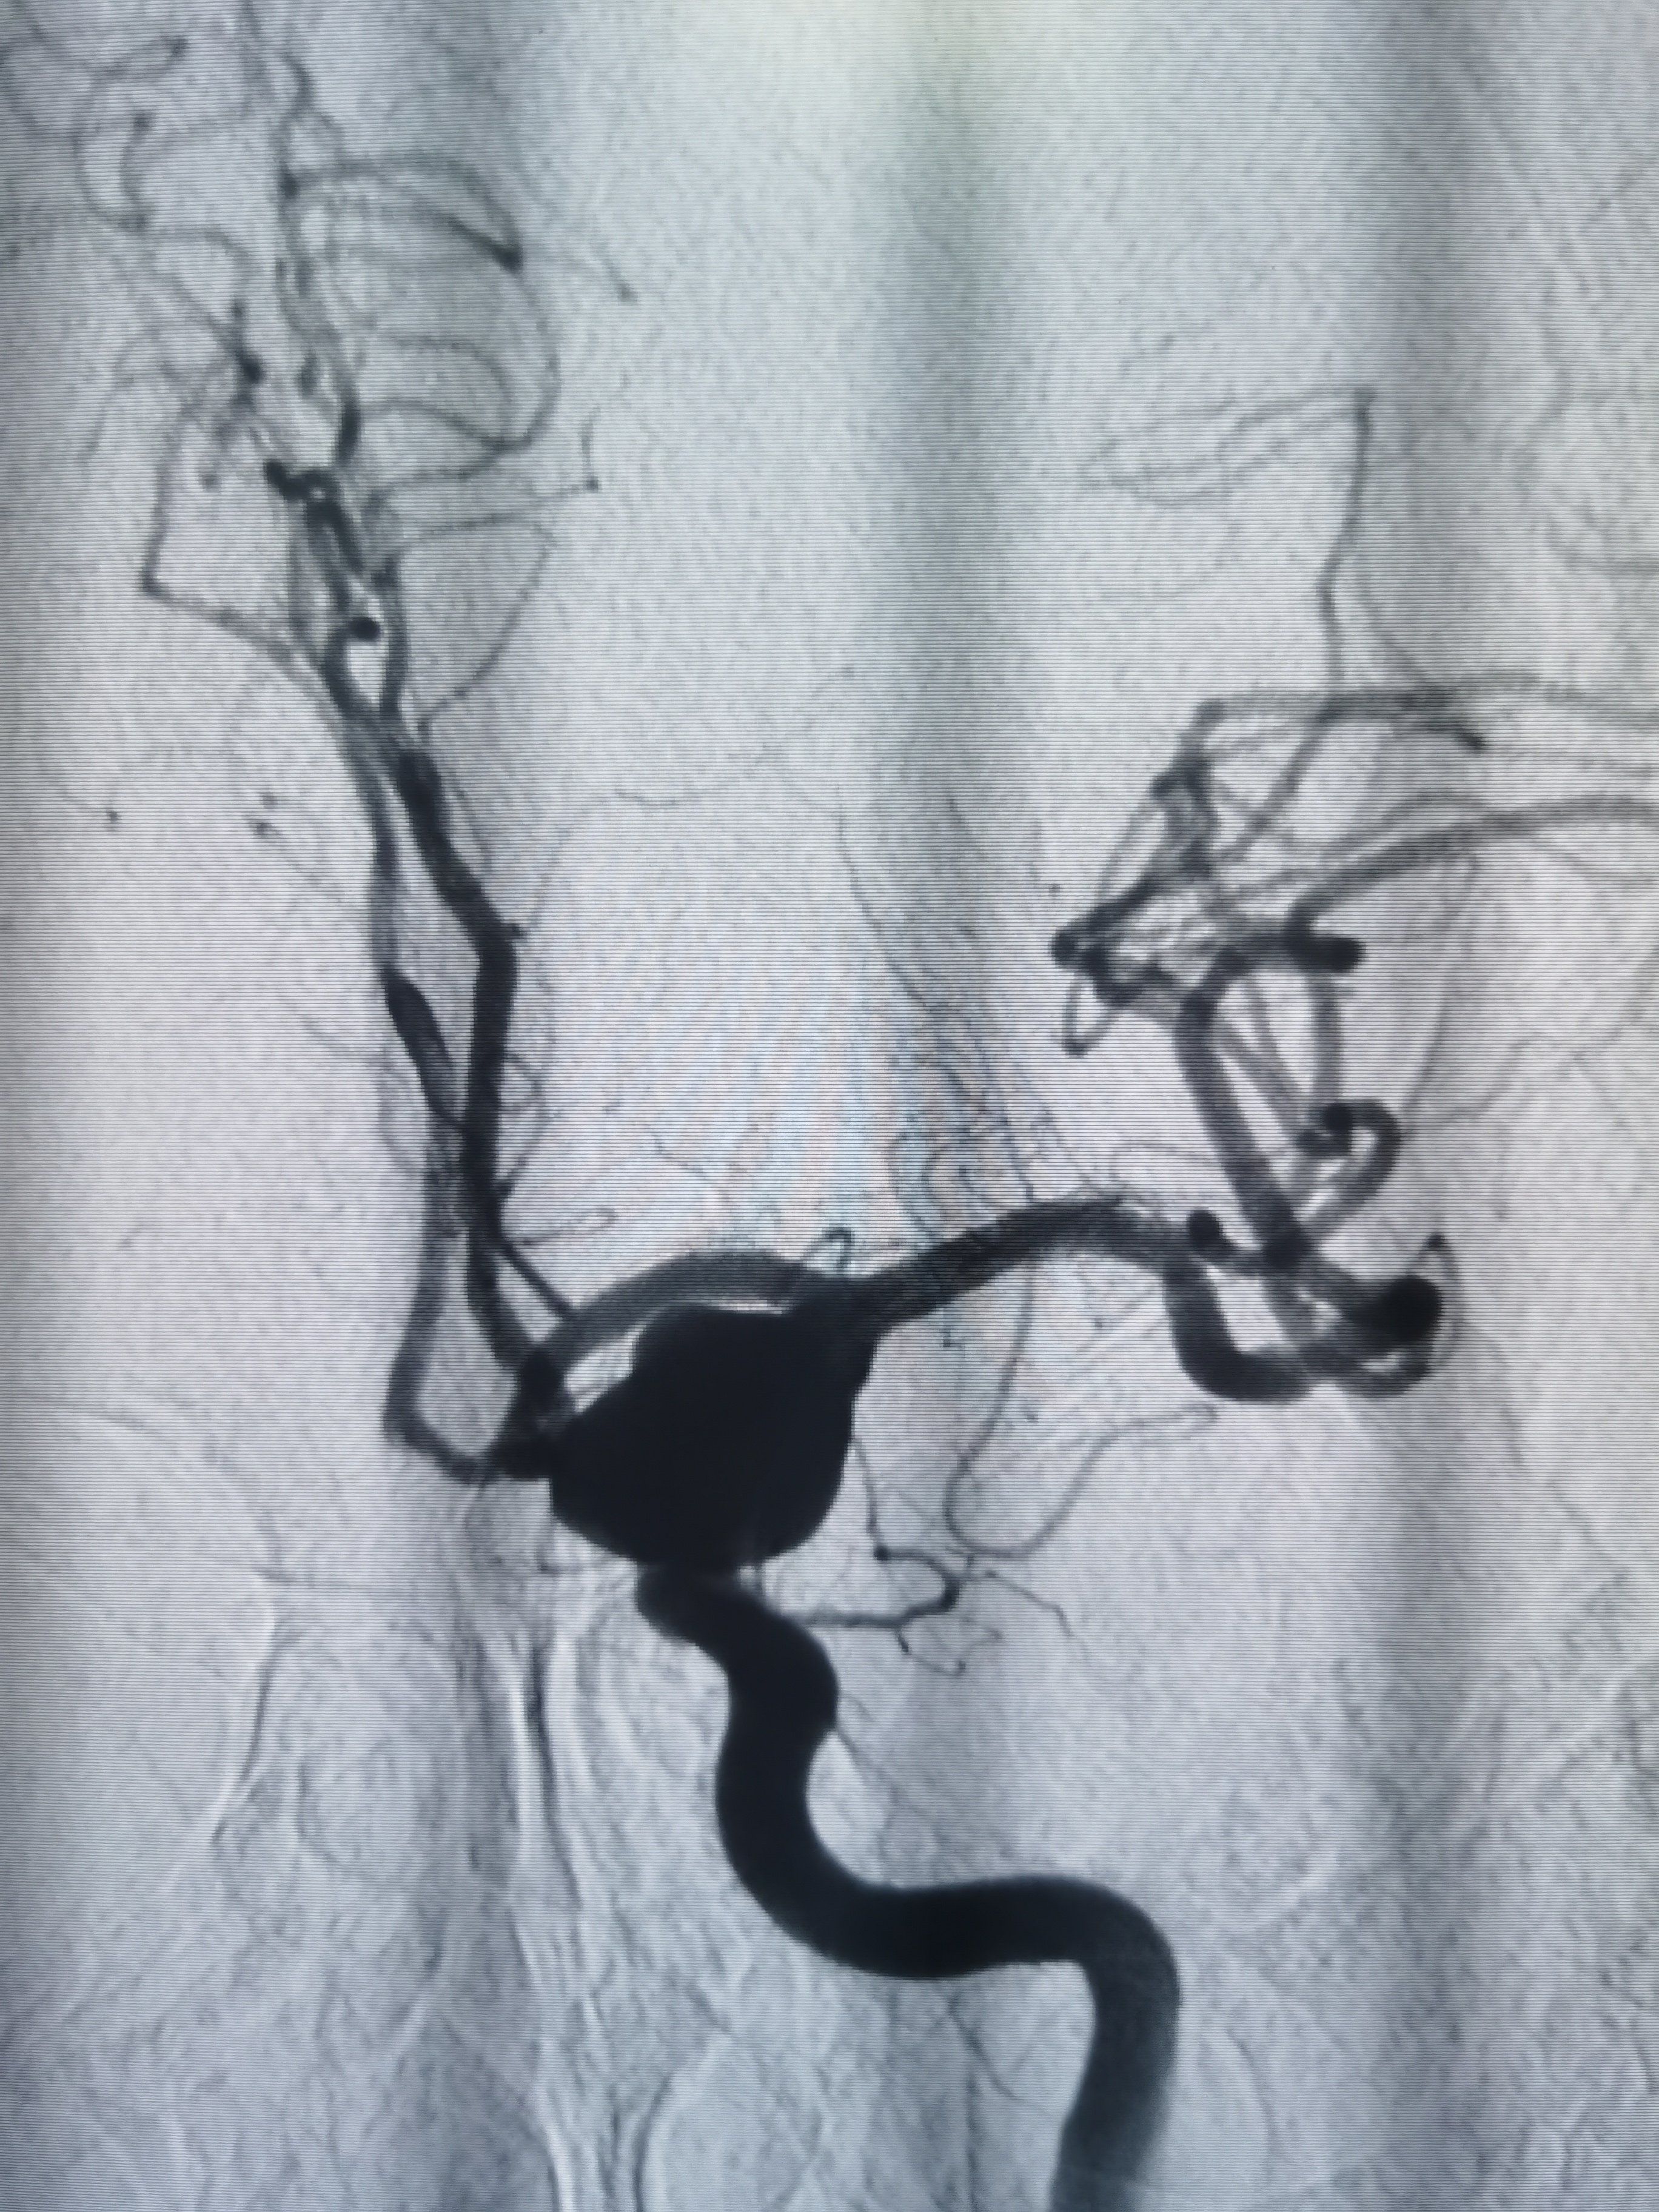

CTA可见左侧颈内动脉颅内段巨大动脉瘤,瘤体12.5*14*9mm。

DSA示右侧大脑中动脉M1远端重度狭窄。

左侧颈内动脉C7动脉瘤改变。